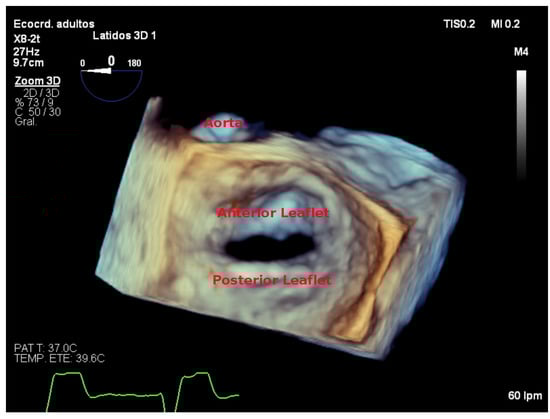

- It measures all three spatial dimensions. Therefore, it is not reliant on plane positioning and does not require geometric assumptions of cardiac structures.

- Images can be rotated and viewed from different perspectives. This allows for a better understanding of the relationship between structures and makes 3D images more intuitive.

7.3. Real-Time 3D Imaging

7.4. Focused Wide-Sector (3D Zoom) Imaging